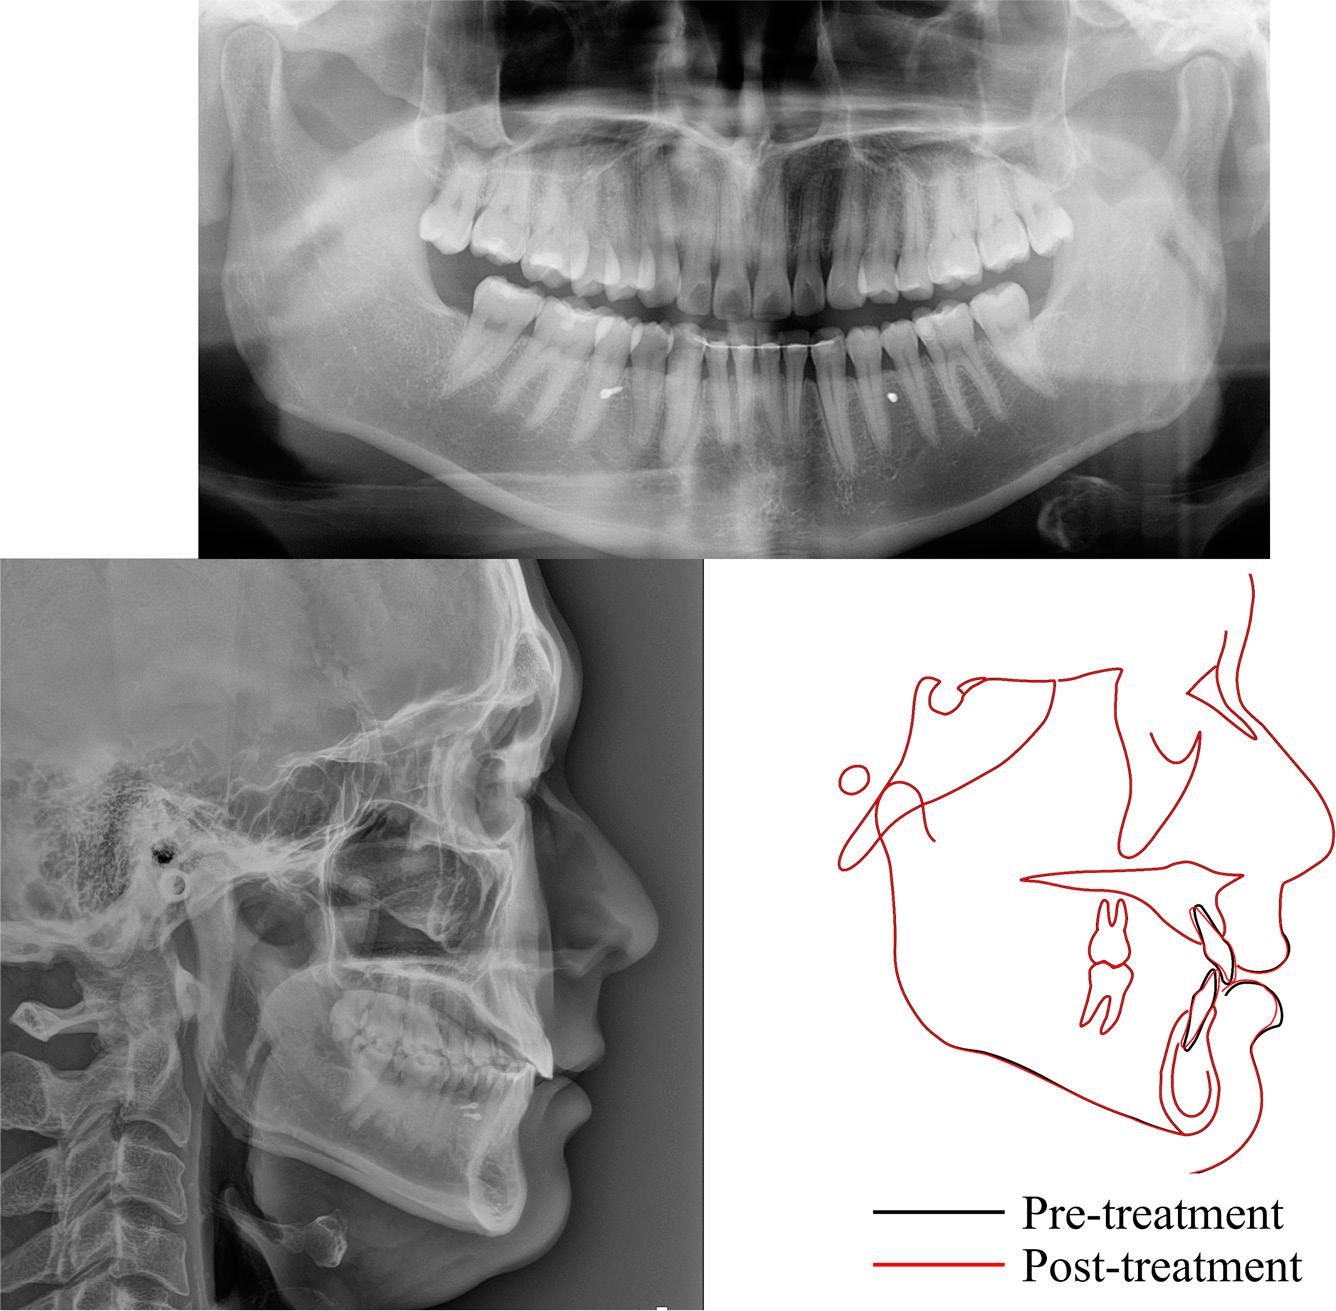

The panoramic radiograph showed a distally angulated left mandibular third molar, while the maxillary third molars had erupted in an upright position (Figure 2). The findings from the lateral cephalogram indicated a Class I skeletal pattern, with a slightly reduced mandibular plane angle (Figure 2, Table I). Additionally, the maxillary and mandibular incisors were retroclined.

Pre-treatment radiographic records, including panoramic and lateral cephalogram.

The panoramic radiograph showed the distal movement of the right mandibular canine root (Figure 11). The post-treatment cephalometric measurements and superimposition of the pre- and the post-treatment films demonstrated that incisal proclination occurred without compromising the facial profile (Figure 11, Table I).

Post-treatment radiographic records, including panoramic, lateral cephalogram, and the superimposition of cephalograms taken at pre- and post-treatment.